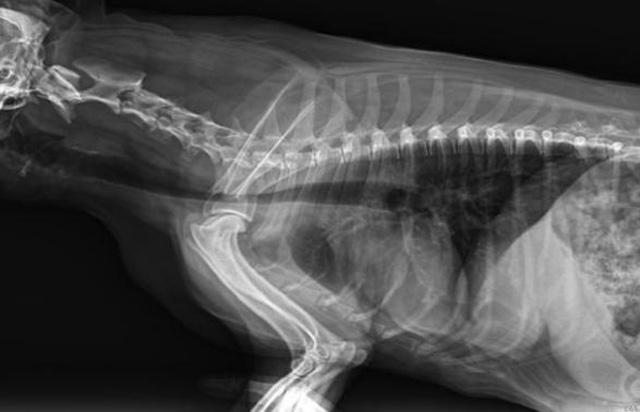

寵物DR是動(dòng)物專(zhuān)用的數(shù)字化攝影系統(tǒng),x線的穿透能力、低的輻射劑量,輻射劑量比X光低:熒光作用和感光作用,可以穿透動(dòng)物身體的結(jié)構(gòu)顯示成像,動(dòng)物的各個(gè)部位成像輔助獸醫(yī)診療。寵物DR采集時(shí)間10ms以下,成像時(shí)間僅為3秒,從檢查到出診斷報(bào)告大約5—10分鐘。較高的空間分辨力和低噪聲率,可獲得高清晰圖像。 DR成像數(shù)字化處理的特點(diǎn)可進(jìn)行后處理。提高了病灶的檢出率,這樣大大提高檢查的準(zhǔn)確率提高診斷準(zhǔn)確率避免漏診誤診等情況。